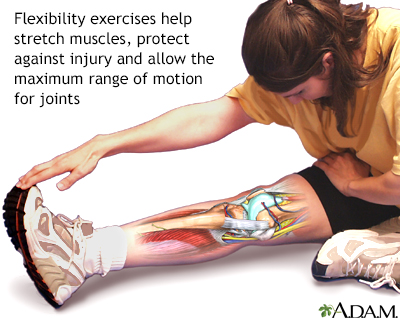

Product Name: Heel wedges for bursitis sale

Running with heel bursitis should I do Achilles wedge stretches for Haglunds sale, Retrocalcaneal Bursitis Symptoms Causes Treatment sale, Insoles for Heel Bursitis ShoeInsoles sale, Orthotics for Bursitis SoleScience sale, Dr David Samra Sports Medicine Specialist Sydney sale, Retrocalcaneal Bursitis Symptoms Causes Treatment sale, Retrocalcaneal Bursitis Treatment OSMO Patch US sale, Retrocalcaneal Bursitis SLO Motion ShoesSLO Motion Shoes sale, Bursitis of the heel Information Mount Sinai New York sale, Heel Bursitis Cause Symptoms Treatment Exercise sale, Amazon Heel Bursitis sale, Heel Bursitis Treatment Arthritis health sale, Heel Bursitis Treatment Long Island Foot Doctors Massapequa Podiatry Associates P.C sale, Medial Lateral Heel Wedge Silicone Insoles Supination Pronation Corrective Heel Insoles Gel Adhesive Shoe Inserts for Foot Alignment Knock Knee sale, Bursitis of the heel Information Mount Sinai New York sale, Achilles Bursitis The Complete Injury Guide Vive Health sale, San Luis Podiatry Group sale, Heel Bursitis Causes and Treatment YouTube sale, Bursitis A Real Pain in the Heel sale, What Is Retrocalcaneal Bursitis Symptoms Causes Prevention Treatment sale, Heel Bursitis The Foot and Ankle Clinic sale, Retrocalcaneal bursitis Physioline sale, 12 Best Execise for Retrocalcaneal Bursitis Samarpan Physiotherapy Clinic sale, Heel Bursitis The Foot and Ankle Clinic sale, Retrocalcaneal Bursitis Achilles Tendon Swelling Heel Pain sale, Retrocalcaneal bursitis Physioline sale, Retrocalcanel Bursitis 4 Life Podiatry sale, 416 Running with heel bursitis should I do Achilles wedge stretches for Haglunds DOC sale, Achilles Bursitis Heel Pain PhysioAdvisor sale, Achilles tendon support with septate friction pads and insulated heel wedge. Septate pads gently massage the oedema away from the paratenon during sale, Achilles Bursitis Causes Symptoms Treatment sale, Can Achilles Bursitis Be Treated Without Surgery Island Foot Clinics sale, Medi AchiMed SAND Achilles Tendon Support with Gel Heel Cup Brace Bursitis Sports I 18 20cm Amazon Health Personal Care sale, Retrocalcaneal bursitis The ankle Biomechanical problems What We Treat Chiropody Leading chiropodist Podiatrists in Manchester and Liverpool sale, Achilles Bursitis Rehab 49 sale.

Heel wedges for bursitis sale